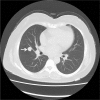

Patient concerns: A 55-year-old woman incidentally detected a space-occupying lesion of right lung in routine health examination. The patient was asymptomatic and there were no positive findings in routine laboratory examination, physical examination, and pulmonary function test. Computed tomography revealed a solitary round mass in the middle lobe of the right lung.